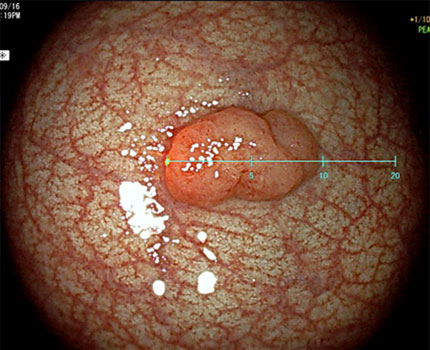

Virtual scaleを用いた生体内における大腸ポリープ径の計測

大腸ポリープはサイズによって治療適応や切除方法が決定されるため、サイズの推定は重要です。しかし、生体内の推定ポリープ径は術者の経験に基づくため、特に初学者ではサイズのばらつきが大きくなります。ワンタッチで画面上にバーチャルスケールが表示され、直接ポリープ径を計測可能な内視鏡が開発されています。これにより初学者でも正確にポリープ径の計測が可能となっています。

直線スケール

円形スケール

(図内の単位はmm)